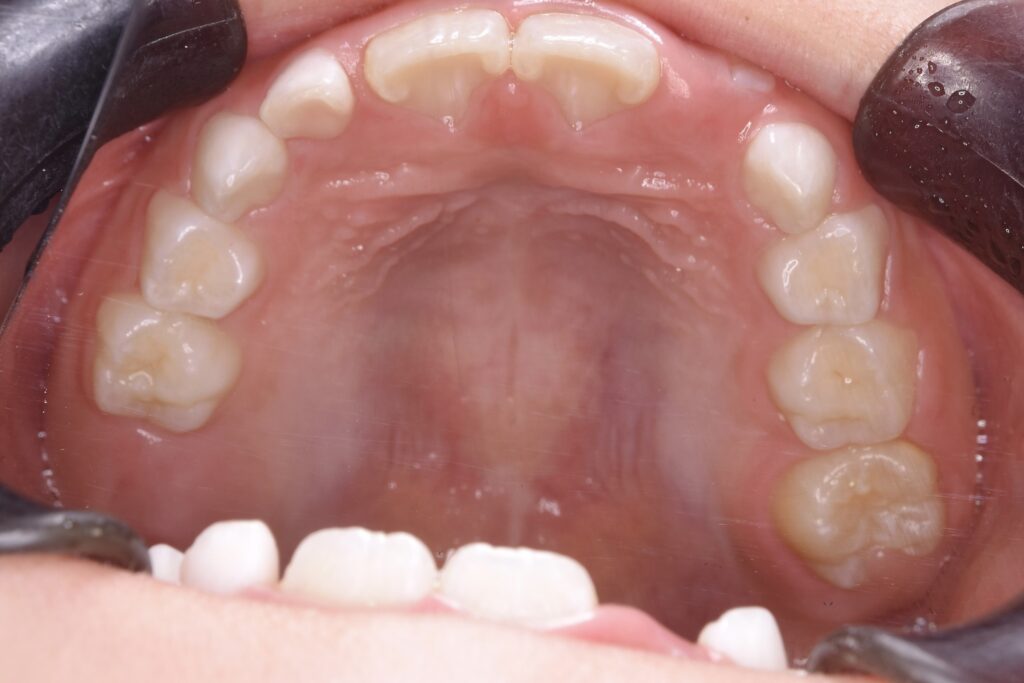

BEFORE

診断名・主な症状

過蓋咬合

治療内容

上下の歯並びの幅を拡げつつ、前歯の関係を改善しました。

使用装置

急速拡大装置

リンガルアーチ

機能的矯正装置(マイオブレース)

抜歯部位

抜歯なし

治療期間

2年 + 後戻り止め期間(5年)

通院回数

25回

費用

50万円程度(税別)

リスク・副作用

痛み、歯肉退縮、歯根吸収、抜歯に伴う出血や腫れが生じることがあります。